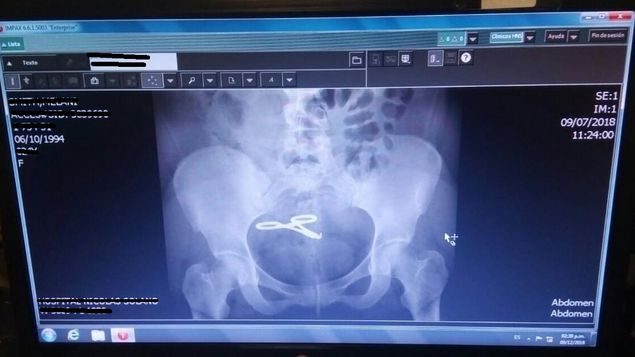

La mujer de 35 años contó que vivió cuatro años con una pinza dentro de su vientre tras una cesárea que le practicaron en el Hospital Santo Tomás.

Tras la mala praxis la mujer sufrió una trombosis venosa profunda que casi termina con un paro cardiorespiratorio. Foto: redes sociales.

La bocatoreña Melanie Smith, de 35 años, casi muere luego de que especialistas de la maternidad del Hospital Santo Tomás, le dejaron en su vientre una pinza cuando le realizaron la cesárea mediante la cual dio a luz a su criatura.

La denuncia que Melanie Smith realizó la sustentó en los documentos de su historia clínica en los que se puede apreciar que en hallazgos postoperatorios dan fe de la causa por la cual ella perdía sangre.

Sacar la pinza de su vientre es el menor de los problemas que enfrenta actualmente, pues como la pinza permaneció cuatro años dentro de su abdomen, esta se le adhirió al intestino delgado, razón por la cual tuvieron que extirparle gran parte de este órgano.